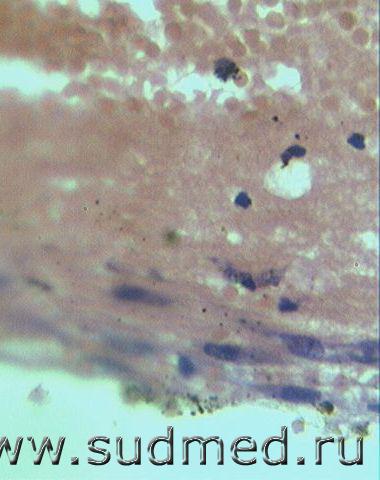

В гематоме лейкоцитов мало, единичные нити фибрина (на фото плохо видно), а клетки (фибробласты?) получились почетче.

Судебная медицина - Прикрепленное изображение Судебная медицина - Прикрепленное изображениеСудебная медицина - Прикрепленное изображениеСудебная медицина - Прикрепленное изображение

Так ведь присутствуют фибробласты в сопряжении с ТМО, есть лейкоцитарный детрит (лейкоцитарные тельца) Правда фибробласты слегка тучноваты (а хорошо ли профиксирован материал?) Вижу один сидерофаг

Давность гематомы в обозначенной зоне более 2-х суток

ТМО,разные эритроциты,фибробласты,нейтрофильные лейкоциты,фибрин,формалиновый пигмент.

Не могу чётко раглядеть,есть ли среди пигмента гемосидерин?Вроде на первом фото внизу справа он есть.

Ой, господа, что-то "гложет меня червь сомнения" (всё же фраза доктора Немо стала крылатой) позвольте с Вами не согласиться, с обоими, ну, с чего Вы взяли, что клетки на первом, втором и четвертом фото фибробласты - связи с самой оболочкой нет, выраженных реактивных изменений в самой оболочке нет, может это эндотелиоциты, чтобы развеять мои сомнения не мешало б покрасить на соединительную ткань, хоть по ван-Гизон.

По-поводу сидерофагов и гемосидерина - забываем, господа, забываем - желтая кровяная соль в таких делах никогда не мешает (Перлс)

С фибрином на третьем фото, не спорю, но какой он - рыхлый, плотный, явно это не тонкие нити.

Ладно, это всё придирки, может реактивные изменения в самой оболочке лучше посмотреть?